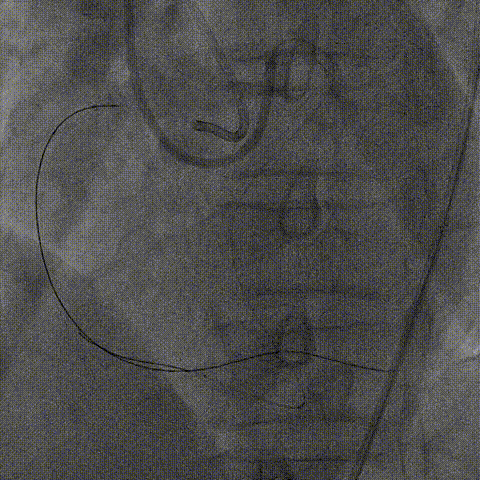

右冠造影:右冠近段完全闭塞,可见大量桥侧枝血管,结合冠脉CTA考虑闭塞段病变合并钙化,同时结合左冠血管扭曲考虑右冠1-2段转弯处存在血管成角扭曲可能;闭塞段入口并不明确,故J-CTO评分2-3分。

1、考虑右冠自身桥侧枝血管供应远段,可先行左冠血运重建后择期开通右冠;右冠闭塞 段>20mm同时合并钙化,术中可先尝试正向介入治疗,必要时启动逆向介入治疗。

2、右冠闭塞段入口不明,近段血管不足以支撑血管内超声导管进入,故对于入口的多投照体位评估尤为重要,若近段入口进入困难,术中可启动BASE技术主动进入内膜下完成与逆向导丝交汇;考虑血肿控制、闭塞段钙化及提高手术效率,术中可尽早使用导引延长导管(本病例选用6F Telescope™导引延长导管)。

1、左冠选用6F EBU3.5指引管,Runthrough导丝前降支锚定保护;右冠SAL 0.75指引管,6FTelescope™导引延长导管备用。

2、正向介入器械:Finecross微导管(130cm);XT-A导丝尝试寻找闭塞段入口及微通道,UB3尝试进入远段真腔失败,保留正向导丝启动逆向介入治疗。